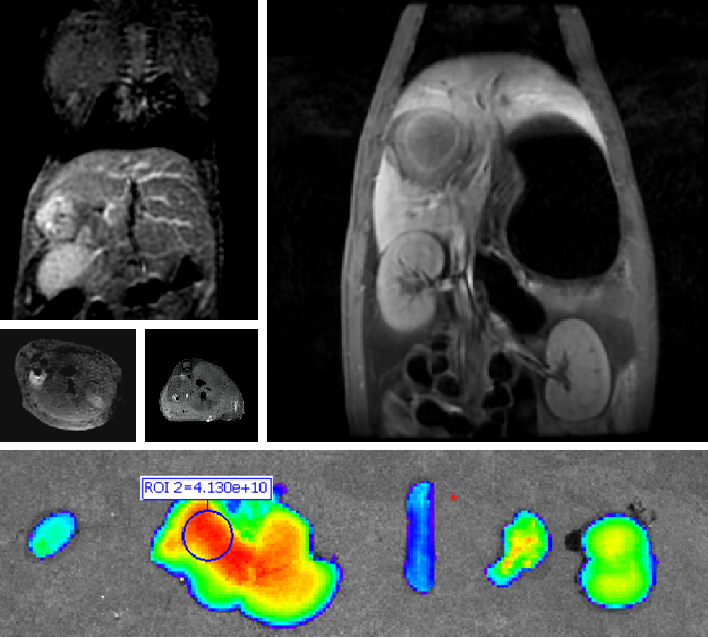

创新双模态造影剂(PL002)

mg电玩娱乐在线网址自主研发的双模态造影剂PL002,已经获得美国FDA临床试验批件。PL002的研制首次提出通过整合磁共振技术,弥补现有荧光染料假阳性率高、透射深度有限等的短板,进而提升手术的精确性,降低手术过程中的风险,是全球首个获批临床试验的荧光/磁共振双模态造影剂。本项目预示着海南普利在造影剂领域的长期投入,并致力于开展独具特色的差异化国际化创新发展路径。

640 (10).png